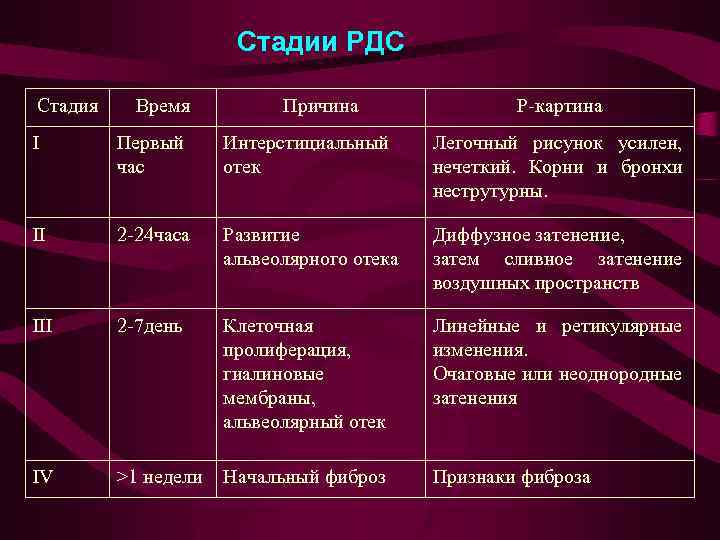

Стадии РДС Стадия Время Причина Р-картина I Первый час Интерстициальный отек Легочный рисунок усилен, нечеткий. Корни и бронхи неструтурны. II 2 -24 часа Развитие альвеолярного отека Диффузное затенение, затем сливное затенение воздушных пространств III 2 -7 день Клеточная пролиферация, гиалиновые мембраны, альвеолярный отек Линейные и ретикулярные изменения. Очаговые или неоднородные затенения IV >1 недели Начальный фиброз Признаки фиброза

Стадии РДС Стадия Время Причина Р-картина I Первый час Интерстициальный отек Легочный рисунок усилен, нечеткий. Корни и бронхи неструтурны. II 2 -24 часа Развитие альвеолярного отека Диффузное затенение, затем сливное затенение воздушных пространств III 2 -7 день Клеточная пролиферация, гиалиновые мембраны, альвеолярный отек Линейные и ретикулярные изменения. Очаговые или неоднородные затенения IV >1 недели Начальный фиброз Признаки фиброза